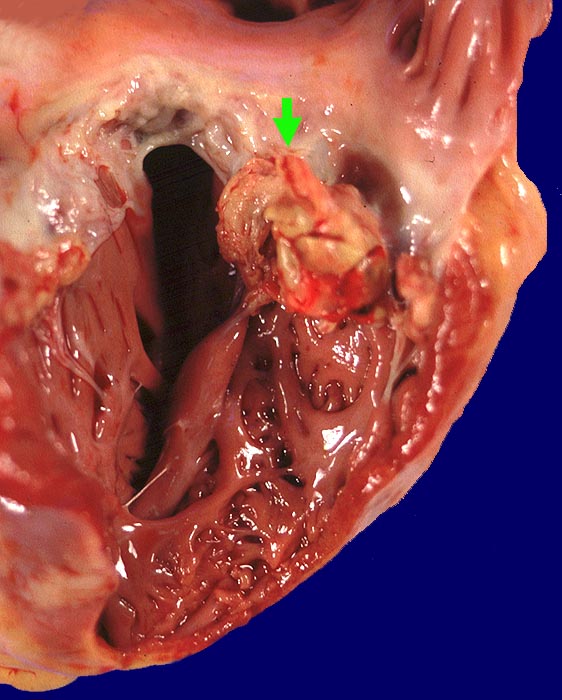

Polypöse Endokarditis

Trikuspidalklappe

Polypöse Vegetation auf der ansonsten intakten Trikuspidalklappe.

Kleine Vegetation auf der Mitralklappe. Nachweis von gram positiven Kokken. Septisch embolische Lungeninfarkte mit Nachweis gram positiver Kokken. Floride chronische Osteomyelitis bei Spritzenabszess am Unterschenkel.

Infektiöse Endokarditis bei iv Drogenabusus. Chronische Hepatitis C.